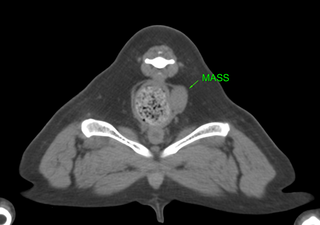

CTによる手術計画

血管走行や臓器との関係によりアプローチを決定します。

前立腺全切除術 Total Prostatectomy

前立腺全摘出術

前立腺が腫瘍に侵されたケース。

恥骨切除後、骨盤腔内にアプローチ、膀胱と尿道吻合術を実施する。術後に化学療法を併用。